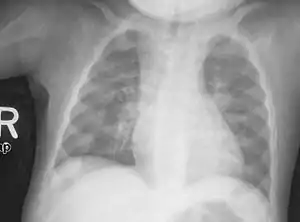

Rickets is a condition that results in weak or soft bones in children, and is caused by either dietary deficiency or genetic causes.[2] Symptoms include bowed legs, stunted growth, bone pain, large forehead, and trouble sleeping.[2][3] Complications may include, bone deformities bone pseudofractures and fractures, muscle spasms, or an abnormally curved spine.[2][3]

An X-ray or radiograph of an advanced sufferer from rickets tends to present in a classic way: the bowed legs (outward curve of long bone of the legs) and a deformed chest. Changes in the skull also occur causing a distinctive "square headed" appearance known as "caput quadratum".[14] These deformities persist into adult life if not treated. Long-term consequences include permanent curvatures or disfiguration of the long bones, and a curved back.[15]